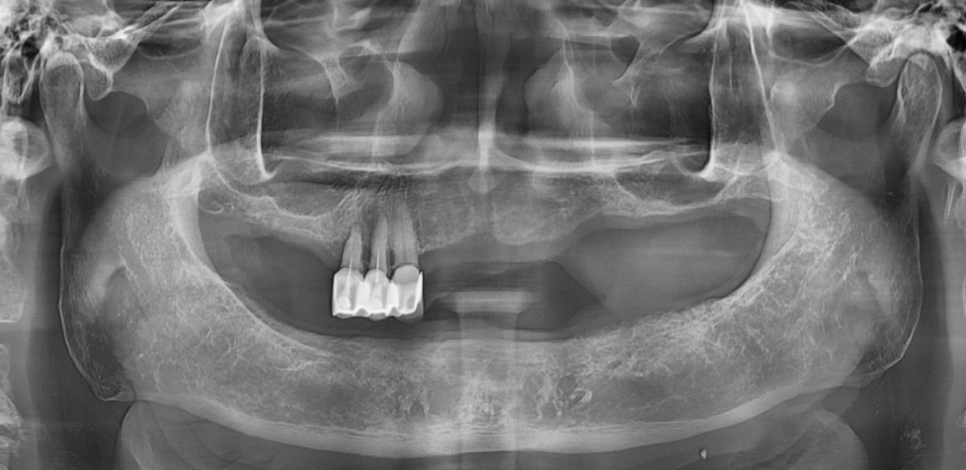

250630 치아가 빠지고 방치하여 정출된 치아

심지어 원래 안좋았던 치아가

다른 치아가 빠져버림으로 인해

안해도 될 일을 자꾸 하게 되어

더 빨리 무너지기도 하죠.